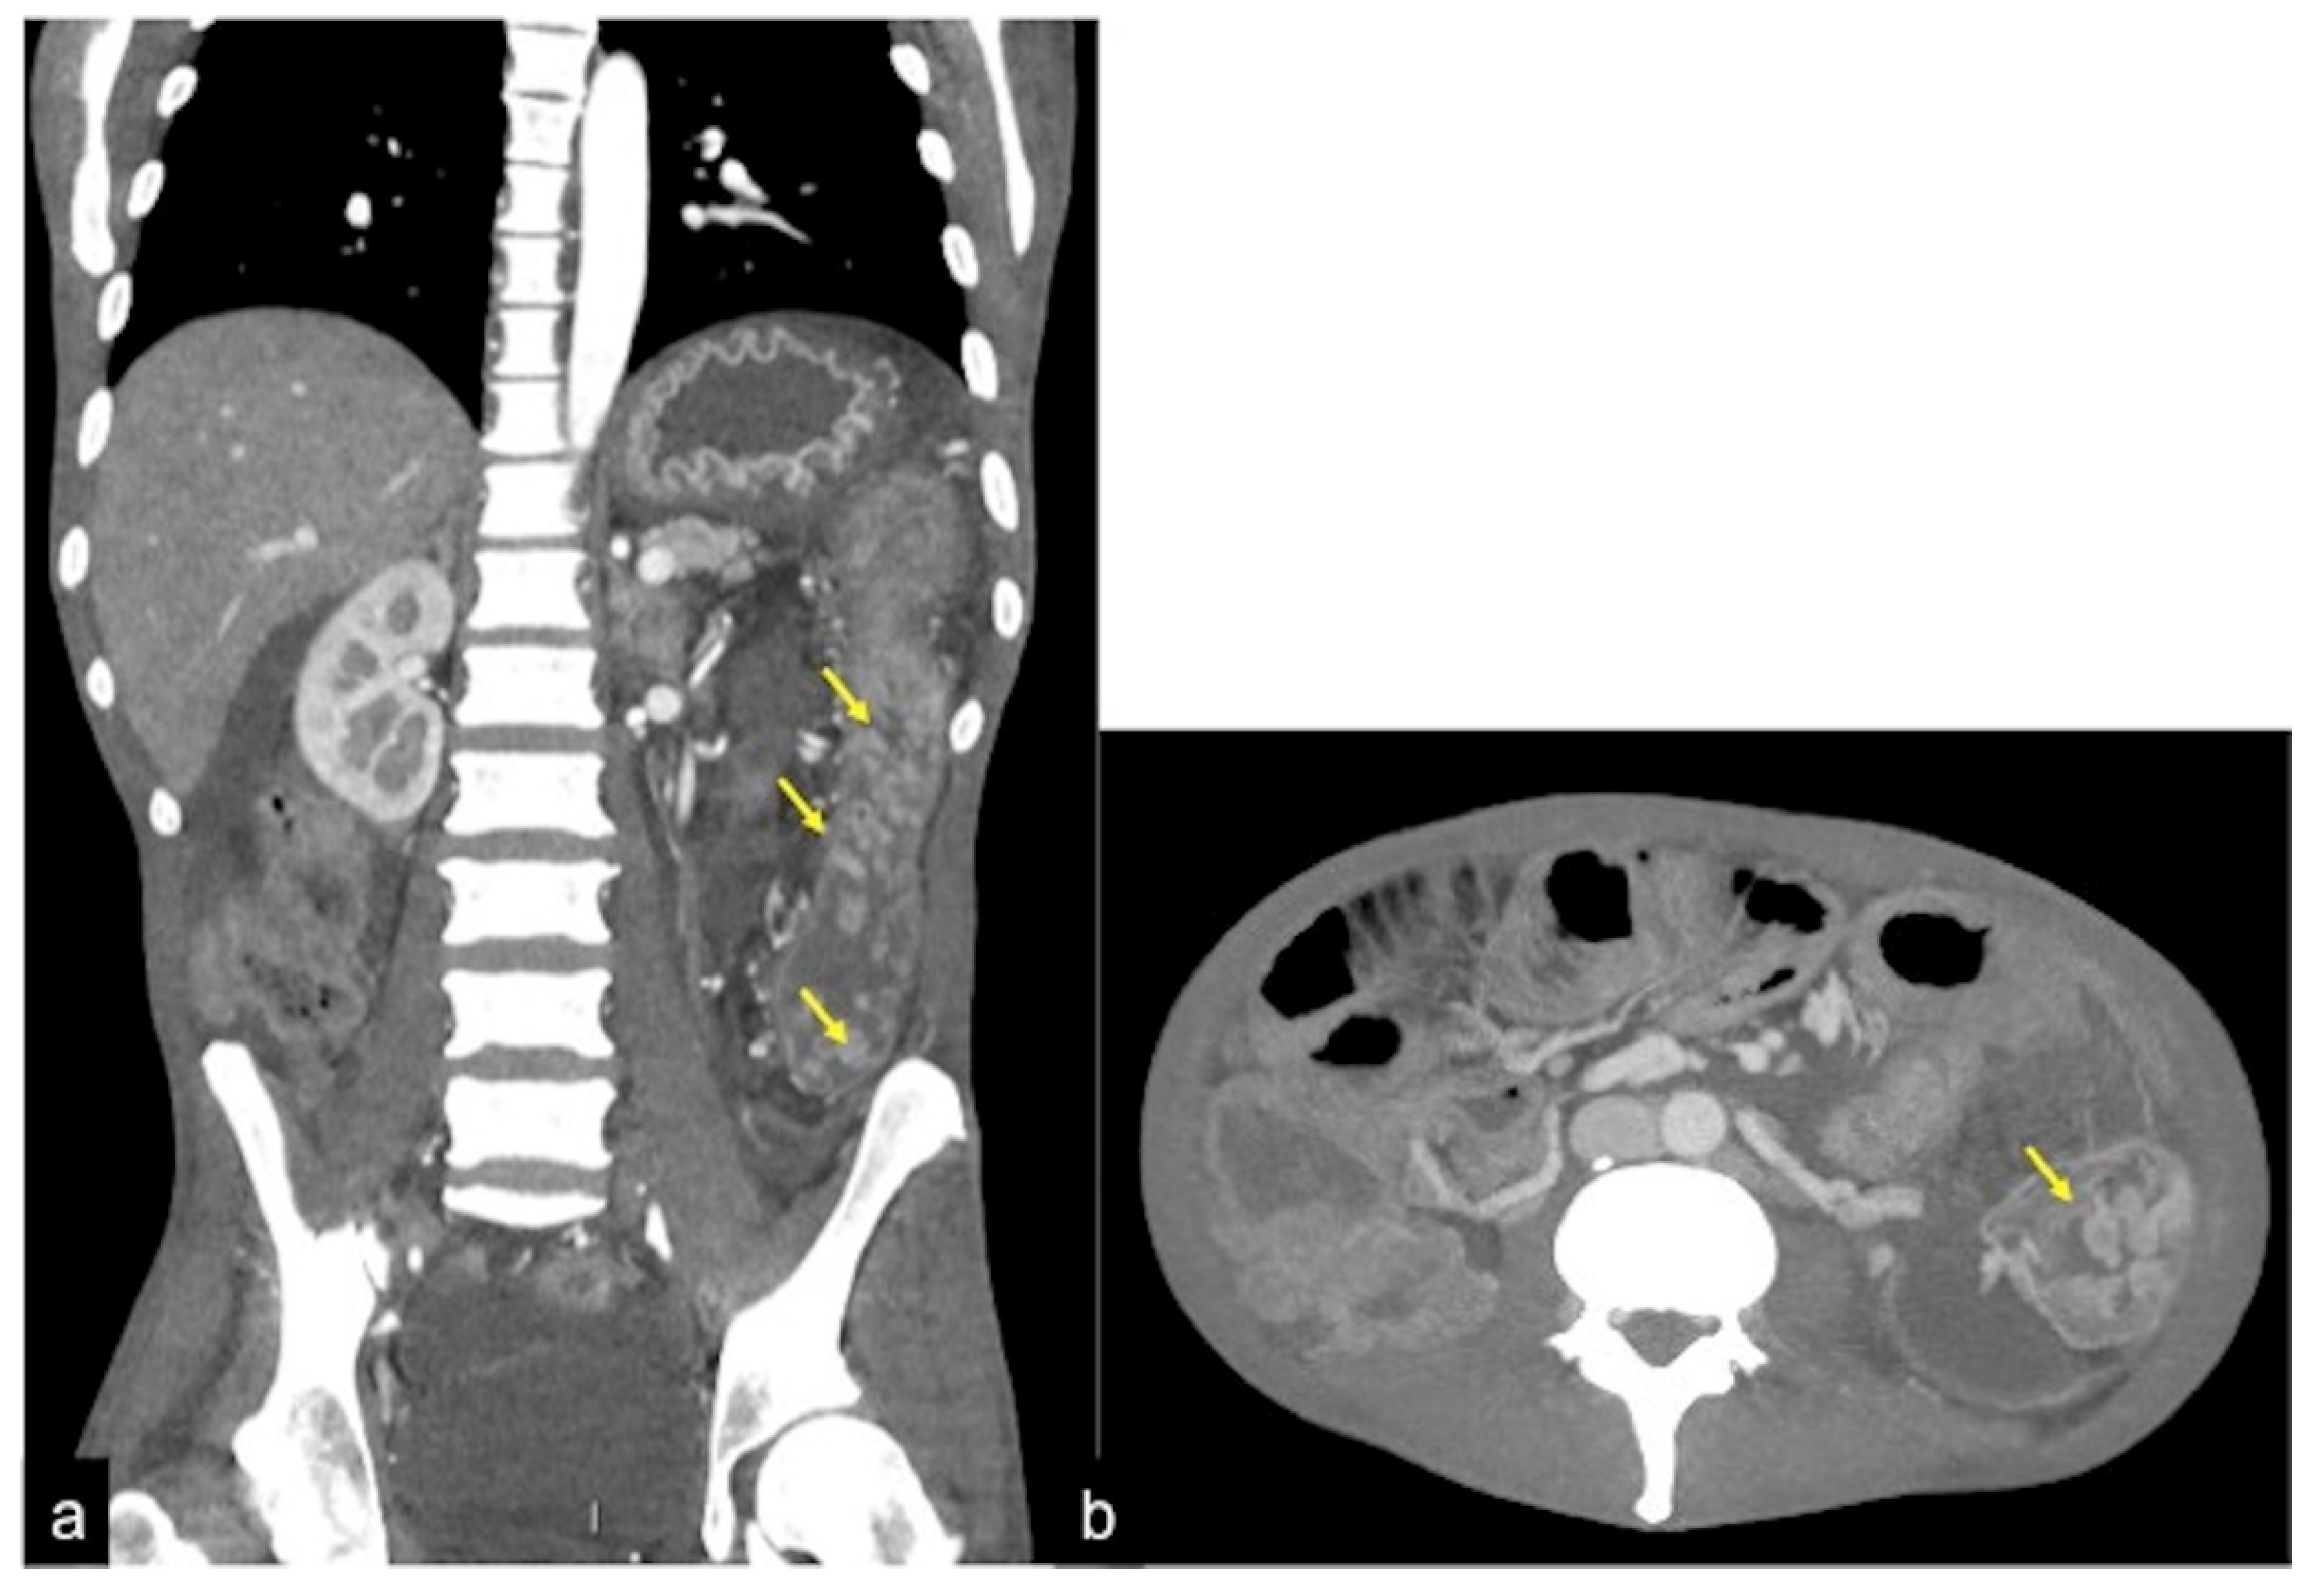

| Aorto-Enteric Fistula (Figure 31) | Bleeding in a patient with a history of surgery for aortic aneurysm. | A connection between the aorta and the intestinal lumen. Absence of adipose cleavage planes. |

| Haemobilia (Figure 32) | Melaena, haematemesis, biliary colic, jaundice, or massive bleeding in a patient with a history of blunt or iatrogenic abdominal trauma. | Presence of blood in the gallbladder and biliary tree. |